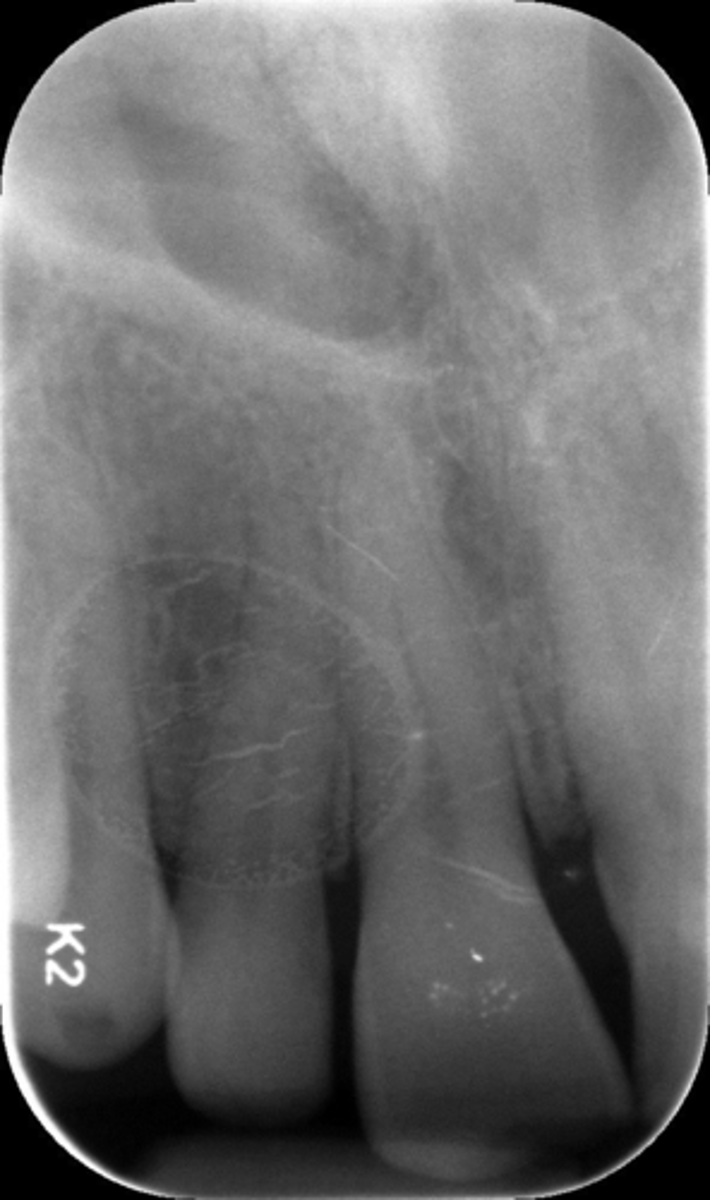

What is this projection of?

Premolars projection

What is this error?

Wrong film direction, backwards, positive angulation, wrong film size, no open contacts